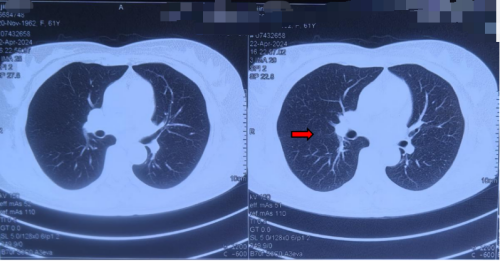

坚持治疗9个月后复查CT,李女士原右肺结节直径缩小至5mm,密度明显减低;继续坚持中药调理1年后,2025年4月最新复查显示结节进一步稳定缩小,未见新发病灶。同时咳嗽、气短等症状也基本消失,精神状态明显改善。她送来锦旗感慨道:“没想到中药真的能让结节变小,我现在终于能睡个安稳觉了。”

患者服中药9个月后于2024-04-23外院复查肺CT影像图(3im29)